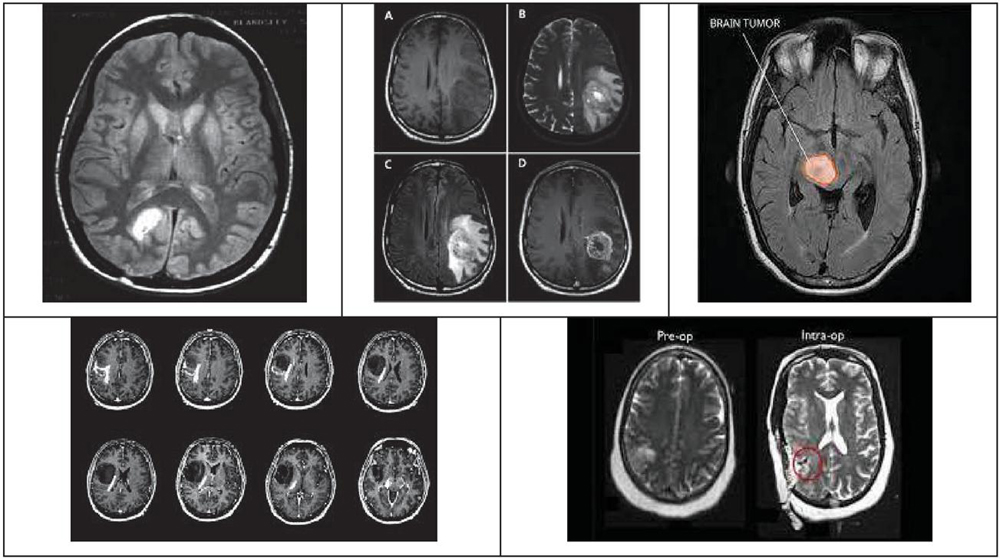

The results provided in this segment were acquired from the proposed Dual Layer Secret image sharing Approach implemented in a PC with the associated details: CPU Intel§Pentium 1.9 GHz, 64-bit operating system, Microsoft Windows 10, 4 GB of RAM, and Math Works MATLAB R2014b stage. Here, all experiments were done utilizing secret and biometric databases, while each containing 200 test images. Few of the secret medical images and the fingerprint images used for biometric fingerprint authentication scheme are given by Figures 4 and 5 respectively.

Figure 4 Secret image database.

Figure 5 Biometric fingerprint image database.